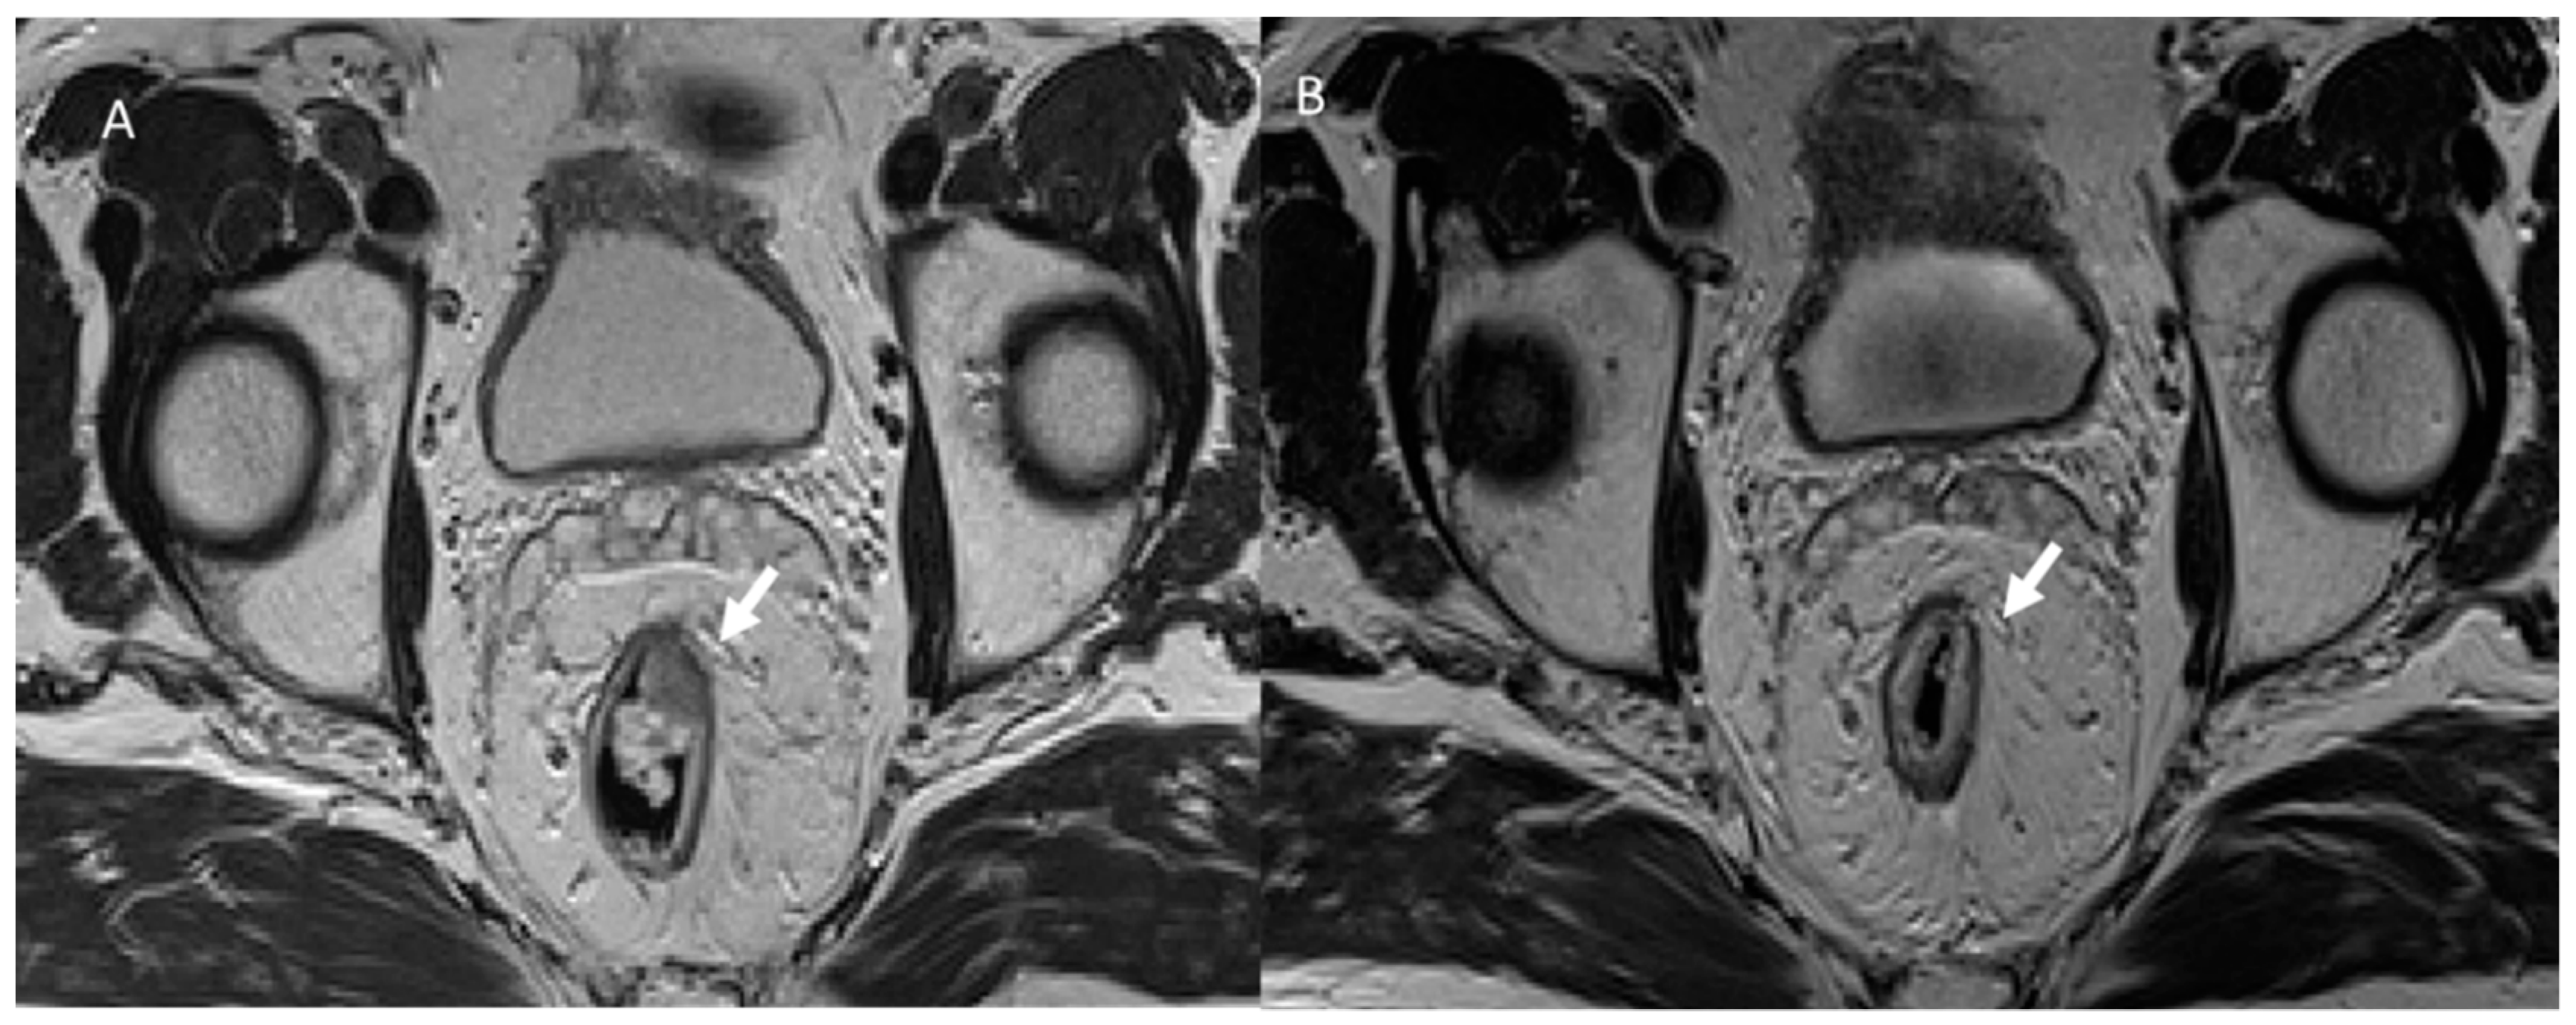

3.2. Fistula

- VanBuren, W.M.; Lightner, A.L.; Kim, S.T.; Sheedy, S.P.; Woolever, M.C.; Menias, C.O.; Fletcher, J.G. Imaging and Surgical Management of Anorectal Vaginal Fistulas. Radiographics 2018, 38, 1385–1401. [Google Scholar] [CrossRef]

- Hori, M.; Oto, A.; Orrin, S.; Suzuki, K.; Baron, R.L. Diffusion-weighted MRI: A new tool for the diagnosis of fistula in ano. J. Magn. Reson. Imaging 2009, 30, 1021–1026. [Google Scholar] [CrossRef] [PubMed]

- Tonolini, M. Elucidating vaginal fistulas on CT and MRI. Insights Imaging 2019, 10, 123. [Google Scholar] [CrossRef] [PubMed]